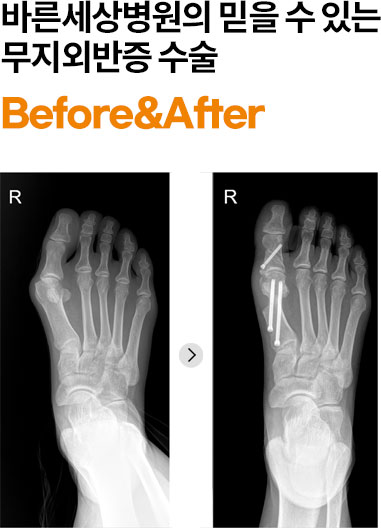

바른세상병원은 최소침습 무지외반 교정술(MICA 또는 MITA)을 시행합니다.